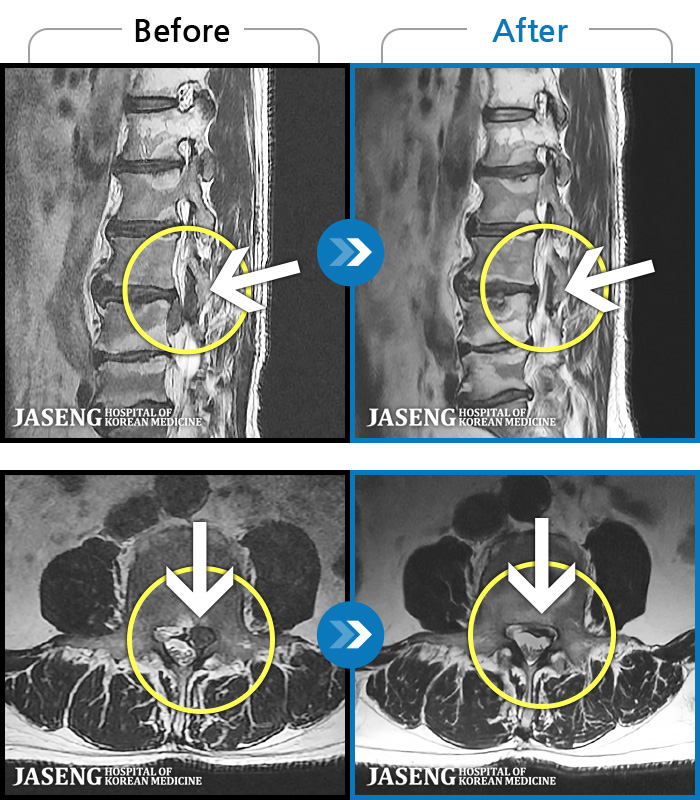

MRI ũ ʸ Ȯϼ.

[뱸] 19.11.28~25.05.06